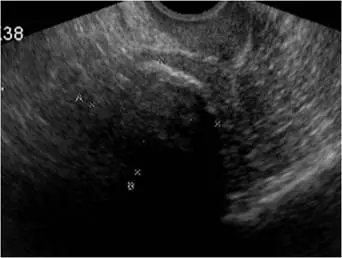

一位 65 歲女性病患,無症狀。腹部 X光片意外發現一個高度鈣化的陰影(如上圖)。 超音波檢查如下圖。其診斷為何:

圖二(骨盆超音波): 超音波顯示一個高回聲(hyperechoic)腫塊伴有後方強烈聲影(posterior acoustic shadowing),影像因聲影而遮蔽深部構造,整體內部細節難以辨識。此超音波表現為嚴重鈣化肌瘤的典型圖像:鈣化的前緣高度反射音波,造成深部完全聲影,使超音波無法清楚評估內部結構。